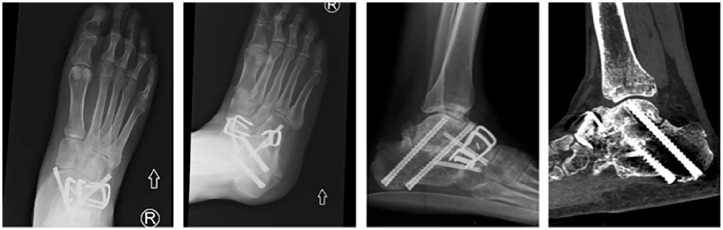

Methods: A 10-year retrospective review of all patients undergoing hindfoot arthrodesis at our institution was performed. Hindfoot arthrodesis was defined as either a triple (subtalar, talonavicular, and calcaneocuboid), double (subtalar + talonavicular), or isolated arthrodesis. Outcomes included fusion success rate and reoperation rate. A postoperative CT confirming the presence or absence of osseous bridging was required for inclusion in the fusion outcome analysis.

Results: We assessed 113 patients who underwent arthrodesis procedures across 128 joints in the hindfoot. There was no significant difference in functional outcomes between screws, staples, or the combination screw and staple constructs used in hindfoot arthrodesis. However, screws alone were associated with a significantly higher complication rate than staple-only fixation (P = .028).

Conclusion: Nitinol staples are effective in hindfoot arthrodesis with respect to fusion success rate and may be associated with decreased revision rates compared with traditional screws only or staple plus screw constructs. Larger studies will be necessary to validate these findings and contribute to an assessment of the usage of these nascent constructs in hindfoot arthrodesis.